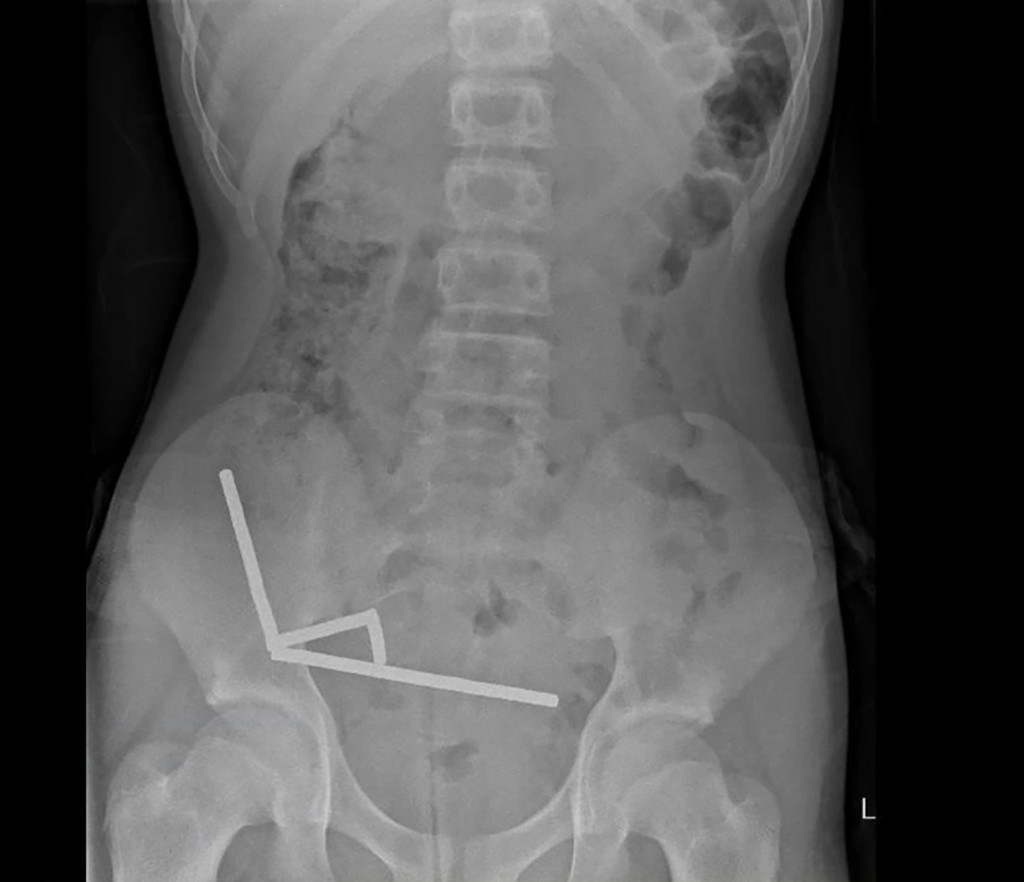

據報這名未透露姓名的少年吞下磁鐵後,腹痛了4天,之後被送往紐西蘭北島的陶朗加醫院(Tauranga Hospital)治療。X光片顯示,磁鐵在少年腸道的不同位置因磁力吸附在一起,形成4條長直鏈。

X光片顯示,磁鐵在少年腸道的不同位置因磁力吸附在一起,形成4條長鏈。法新社